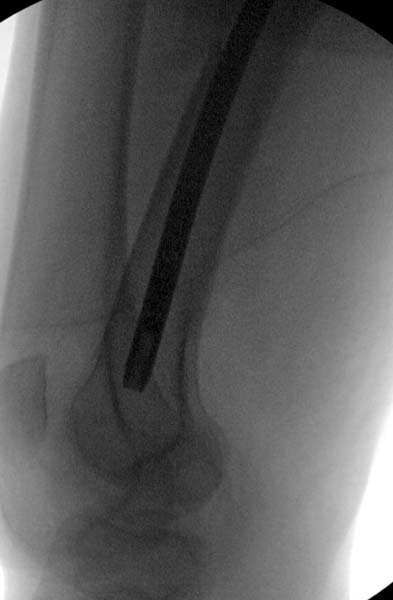

> Остеосинтез бедра не стали делать из-за множественных переломов ребер с

> ушибом грудной клетки и поэтом у закончили фиксацию бедра наружным

> фиксатором.

> Около 11.00 вечера больная переведена в реанимацию, без сознания, но

> стабильная.. На третьий день провели стабилизацию перелома бедра

> антеградным остеосинтезом.